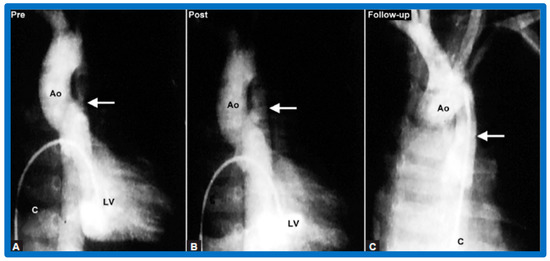

3.3. Aortic Coarctation, Native

4.3. Aortic Coarctation–Native

Revisit BA in the Neonate and Young Infant